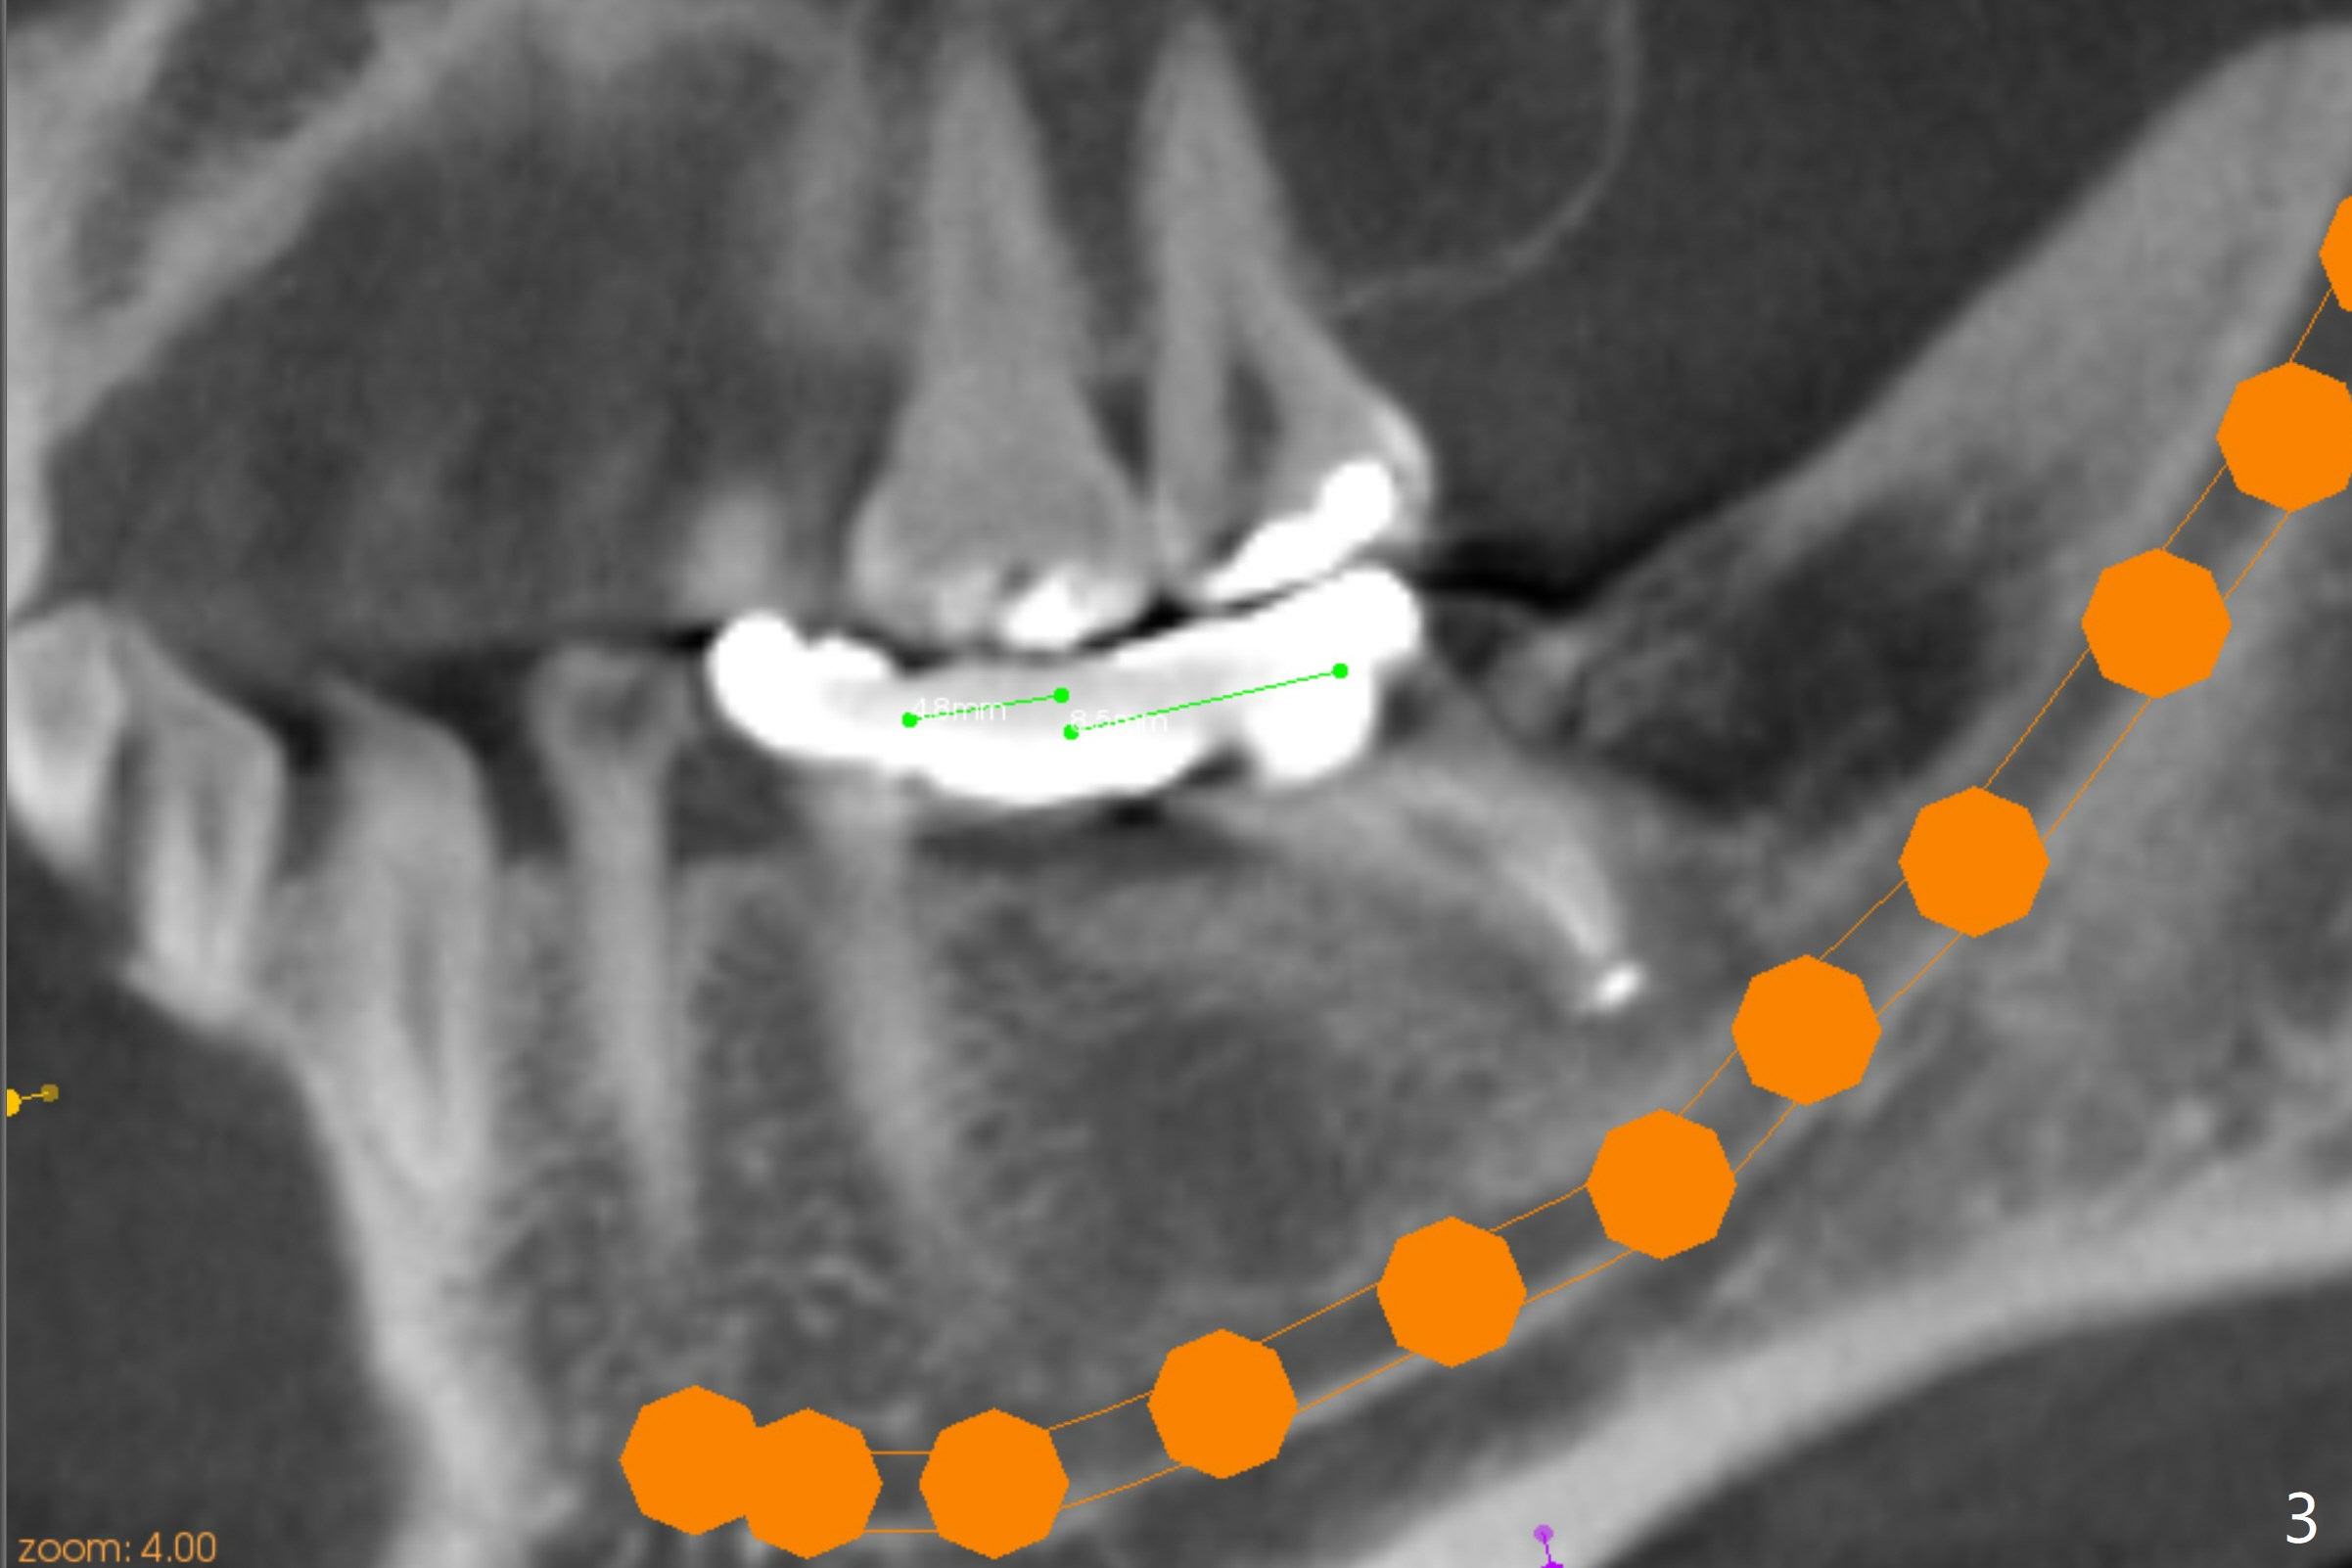

A 45-year-old woman returns to seek treatment for the recemented lower left FPD with open margin at #18 (Fig.1 *). It appears that two implants will be placed (Fig.2,3). Because of the narrow crest at #19, the ridge will be reduced before placement of a 4.5x7(4) mm Magicore (Fig.4). A 5x9(2 or 3) mm one will be placed in the mesial slope of the extraction socket (Fig.2,3,5). Alginate impression will be taken for wax up and surgical stent.